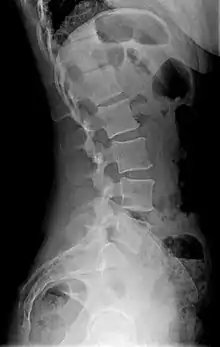

يمكن أن يكون قياس وتشخيص التحدب القطني الزائد صعبا. يكن أن يؤدي اندماج معالم نهاية لوحة العمود الفقري عن طريق الانصهار إلى صعوبة القياس التقليدي للتحدب القطني الزائد. لأن مستويات L4-L5 و L5-S1 تشارك بشكل أكثر شيوعا في إجراءات الاندماج، أو مفصلي، والمساهمة في التحدب القطني الزائد العادي، ولذلك فإنه من المفيد تحديد وسيلة قابلة للتكرار ودقيقة لقياس التحدب القطني الزائد عند هذه المستويات.[6][7]

يوجد علامة واضحة على التحدب القطني الزائد وهي قوس كبير بشكل غير طبيعي من أسفل الظهر ويظهر الشخص كمن لديه انتفاخ في المعدة والأرداف. يتم التشخيص الدقيق للتحدب القطني الزائد من خلال النظر في التاريخ الطبي الكامل، والفحص البدني وغيرها من التجارب للمريض. وتستخدم الأشعة السينية لقياس انحناء قطني، ويتم اجراء مسح للعظام من أجل استبعاد الكسور والعدوى المحتملة، والتصوير بالرنين المغناطيسي (ت ر م) يستخدم لاستبعاد إمكانية تشوه الحبل الشوكي أو الشذوذ العصبي، ويتم إجراء التصوير المقطعي (ت م) للحصول على صورة أكثر تفصيلا من العظام والعضلات وأجهزة منطقة أسفل الظهر.[8]